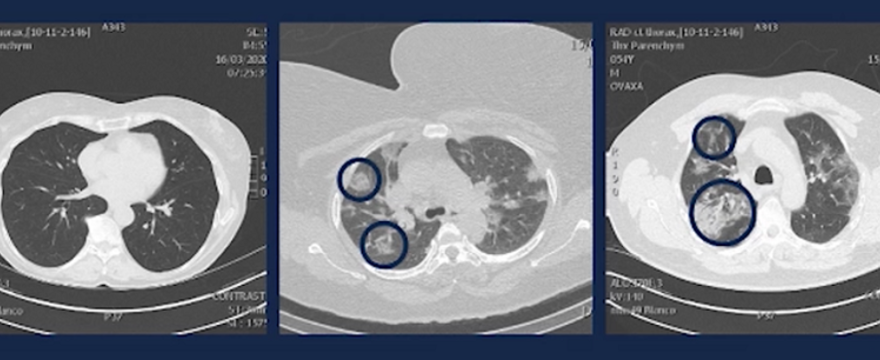

Rodzice uważajcie na siebie! Lekarz pokazał skany płuc młodych ludzi zarażonych koronawirusem - Artykuł